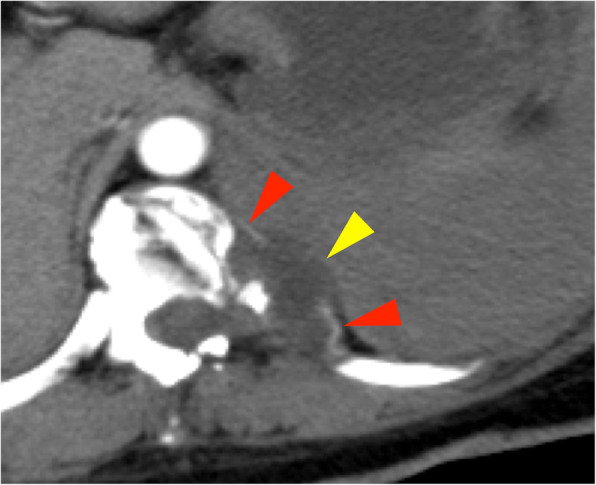

On arrival, she was conscious with a blood pressure of 110/90 mmHg and pulse rate of 90 beats/min. Her hemoglobin level was 10 g/dL and oxygen saturation was 97% with 10 L/min oxygen delivered via mask. Chest radiography revealed a massive left pleural effusion with left-to-right mediastinal shift (Fig. 1). Chest computed tomography (CT) revealed a left pleural effusion and irregularities of the left 10th intercostal artery (Fig. 2). We suspected hemothorax because the CT value of the effusion was 45 Hounsfield units. Furthermore, CT findings also implied intrathoracic dural ectasia close to the artery. A chest tube was inserted immediately; however, only 400 mL of old blood could be removed, and no further significant discharge was collected though the pleural effusion remained. The patient was hemodynamically stable following fluid resuscitation; however, the fetal heart rate was decreasing, and the fetus was in a critical condition. After obstetric consultation, we performed an immediate caesarean section under general anesthesia; the operative time was 40 min and the volume of blood lost including amniotic fluid was 300 mL.

Fig. 2.

Chest computed tomography showed a massive hemothorax and an irregularly shaped left 10th intercostal artery (red arrow). Intrathoracic dural ectasia was observed close to the artery (yellow arrow)